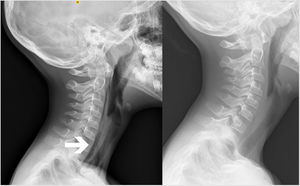

Presentamos el caso de un varón de 8años sin antecedentes médicos, valorado en urgencias por un cuadro súbito de dolor torácico con irradiación cervical, que apareció mientras jugaba al fútbol. El paciente refería empeoramiento con el decúbito y con la ingesta. No refería antecedentes traumáticos recientes ni ingesta de cuerpos extraños. A la exploración física se constató buen estado general, con estabilidad hemodinámica y respiratoria. El paciente no presentó fiebre en ningún momento. No se objetivaron alteraciones óseas, pero sí crepitación subcutánea cervical. No se observó abombamiento de pilares faringoamigdalinos, y la úvula se encontraba centrada. La analítica de sangre mostró leucocitosis y neutrofilia sin elevación de reactantes de fase aguda. Se realizó una radiografía cervical lateral que mostró aire en el espacio retrofaríngeo, sin aumento del espacio retrofaríngeo (fig. 1, izquierda). La nasolaringoscopia no mostró alteraciones. No se realizó tránsito esofagogastroduodenal. El paciente permaneció ingresado 24horas con analgesia y sueroterapia intravenosas y sin oxigenoterapia, con resolución de la sintomatología. Una radiografía ambulatoria a los 15días constató la resolución prácticamente completa del cuadro (fig. 1, derecha).